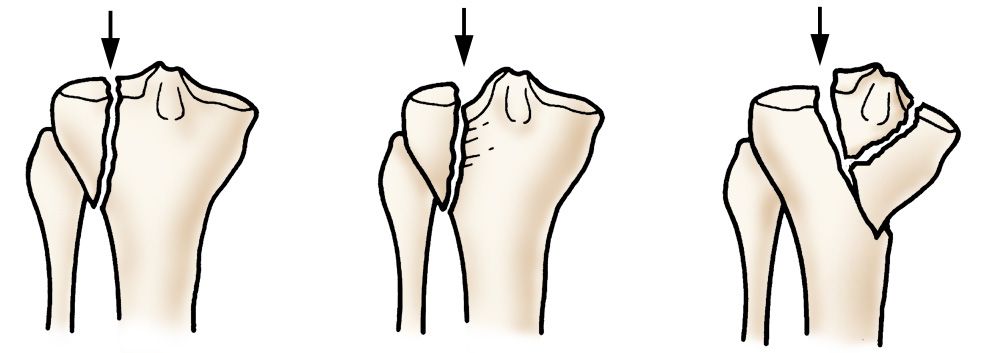

There are several types of proximal tibia fractures. The bone can break straight across or into many pieces (comminuted fracture).

Illustration of different proximal tibia fractures

Examples of different types of proximal tibia fractures.

Sometimes these fractures extend into the knee joint and separate the surface of the bone into a few (or many) parts. These types of fractures are called intra-articular or tibial plateau fractures.